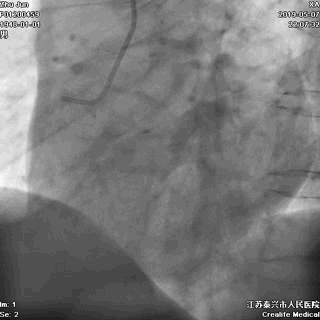

右冠状动脉无严重病变